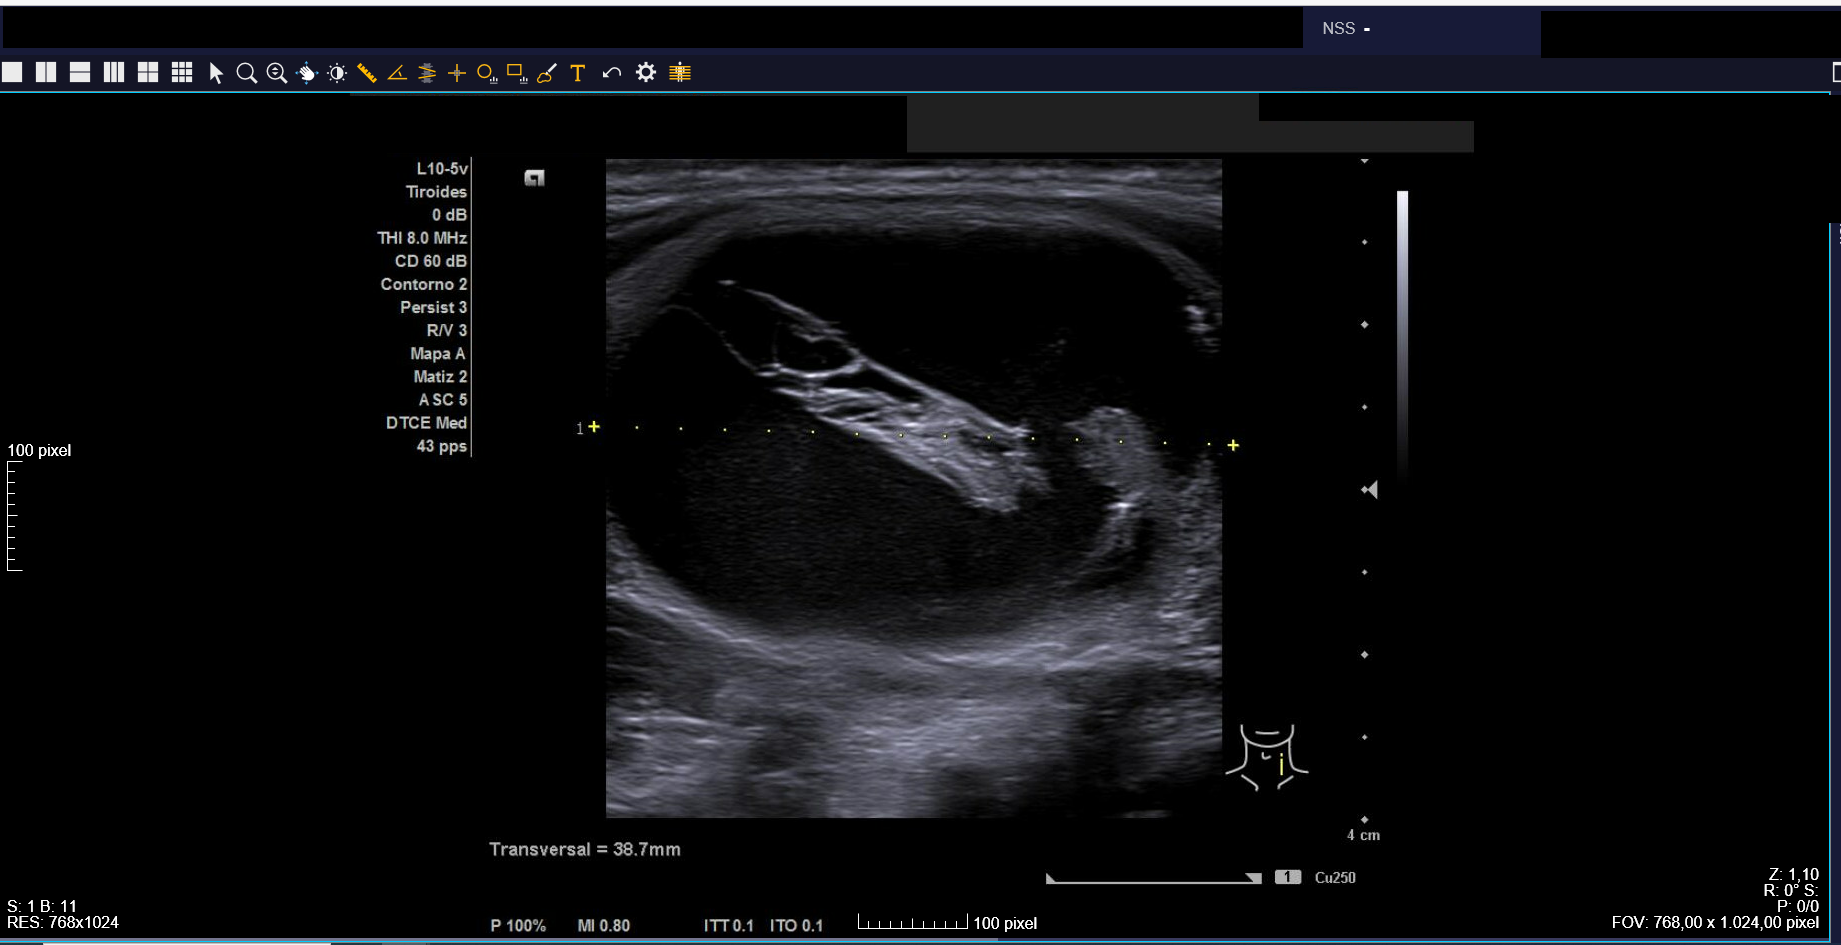

Ecografía clínica: tiroides de tamaño normal con ecoestructura homogénea. En lóbulo tiroideo izquierdo nódulo de 3 cm, anecoico, márgenes bien definidos con imagen hiperecoica en su interior (Imágenes 1, 2 y 3).

Ante clínica y ecografía compatible con hemorragia en nódulo tranquilizamos a la paciente, informándole sobre pronóstico y actitud a seguir. Citamos para seguimiento clínico en 3 semanas, con desaparición del dolor y disminución de tamaño del nódulo.